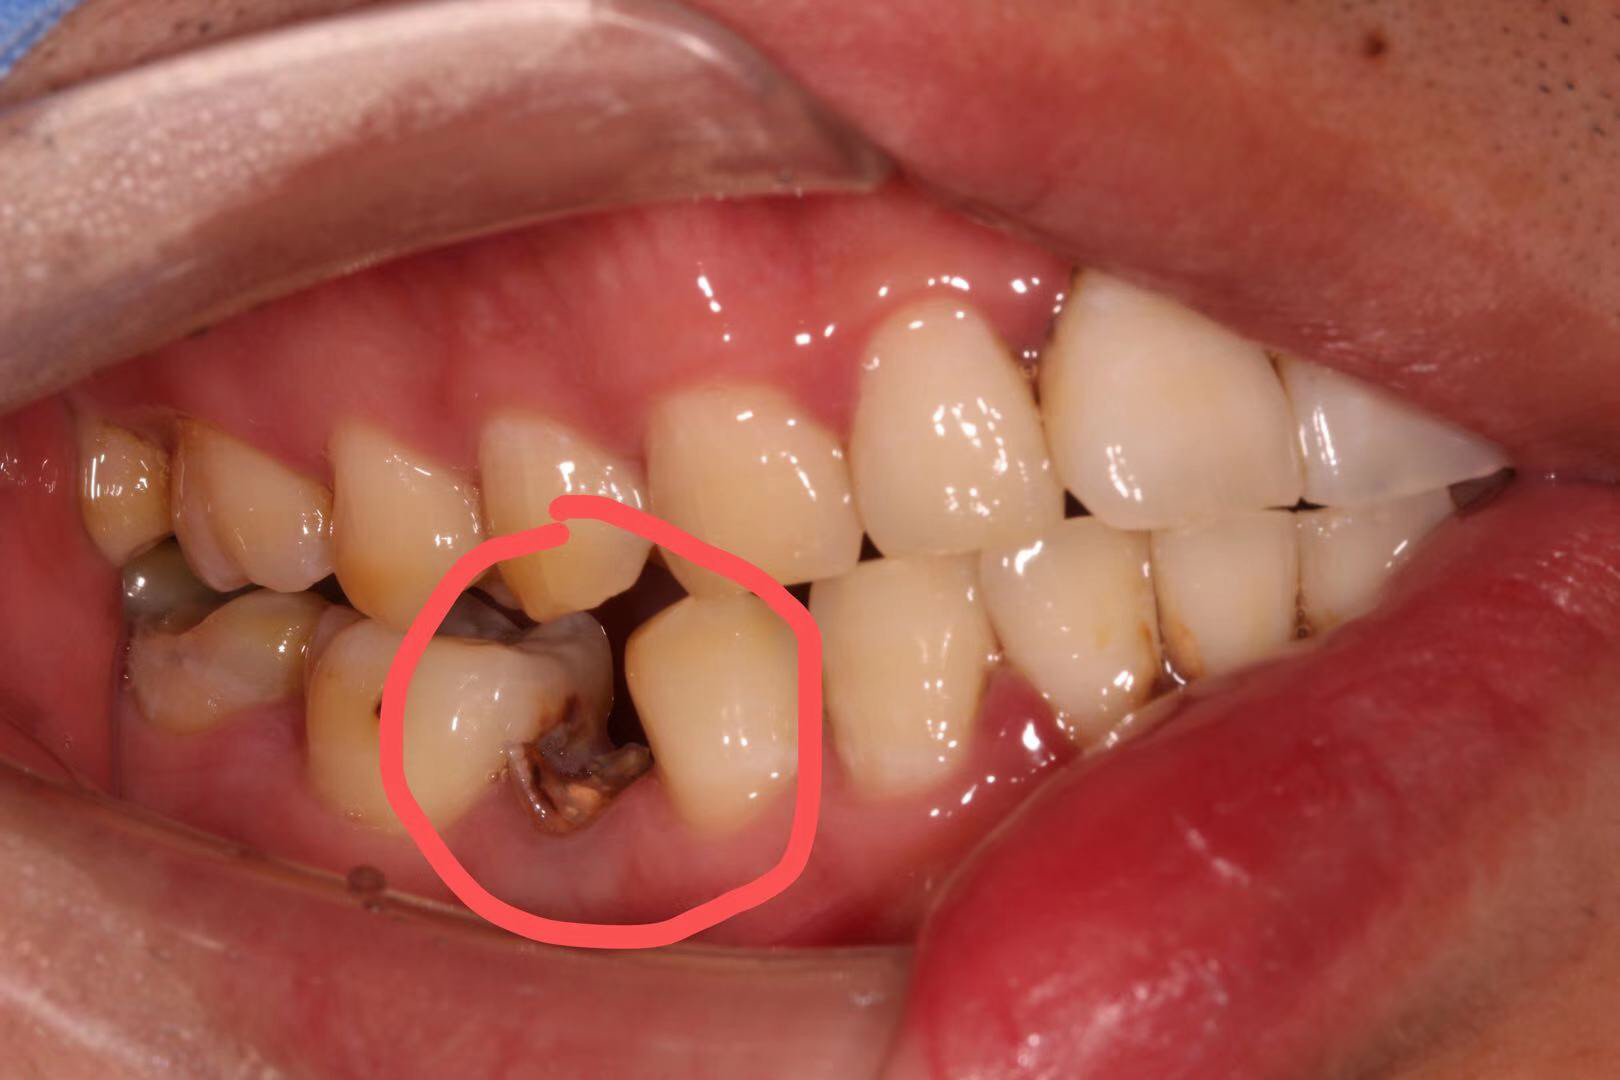

患者是一位刚参加工作的23岁小伙子,右下5号牙由于根管治疗后只是简单补上,没有做高嵌体、全瓷冠等修复方式把牙齿保护起来,吃硬物咬碎且未及时就医,长期腐蚀导致成无法修复的残根,老卢没有采用传统的牙冠桥体修复方式,因为那样对患牙两边的邻牙损伤较大,而是采用老卢最擅长的种植修复,当然老卢做为一名从业20多年的全科医生,其他治疗技术也是不弱的,欢迎牙齿不好的朋友们前来体验。